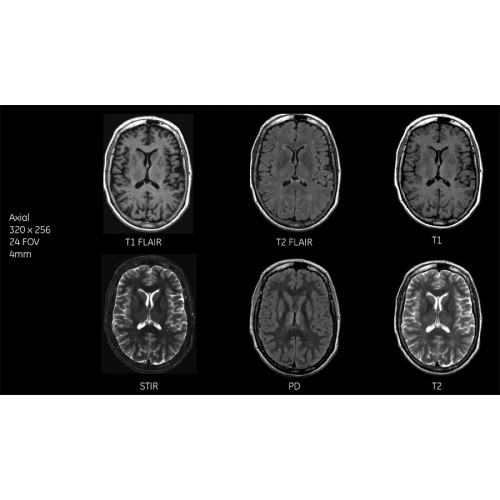

МРТ аппарат GE SIGNA Voyager 1.5T позволяет проводить полный спектр магнитно-резонансных исследований, включая нейровизуализацию, исследования опорно-двигательного аппарата, органов брюшной полости и малого таза, а также специализированные кардиологические программы.